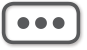

图3-3-12 L 5 /S 1 经椎板间隙入路-不同层面横断位像

A.靶点偏头侧平面;B.靶点操作平面;C.靶点偏足侧平面

图3-3-13 L 4/5 侧方入路-不同层面横断位像

图3-3-14 沿椎弓根轴线扫描的不同层

A.椎弓根偏头侧平面;B.椎弓根中间平面;C.椎弓根偏足侧平面

在扫描产生的多层横断面中选择出最符合穿刺要求的一层,作为设计入路和引导穿刺定位的操作平面,我们将该层称为“靶点操作平面”。根据不同的手术目的选择该平面的要求也不同:避骨入路类手术如经椎板间入路椎间盘靶点定位类,应选择具有最大程度避开神经、血管、脏器、骨质而到达靶点的平面,如图3-3-12中显而易见图B是最合适的平面;经椎间隙侧方入路时的扫描图像中(图3-3-13),图B最合适;而经骨入路类手术如经皮椎体骨折复位外固定、椎体成形术等,应选择椎弓根宽大处的平面,如图3-3-14中图B作为操作平面最合适。CT机架角度扫描的横断位平面自然也是倾斜的,而穿刺定位入路是在该平面内的,因此存在如下关系:CT机架扫描角度=靶点操作平面角度=定位针穿刺时的头足倾斜角度(图3-3-15)。